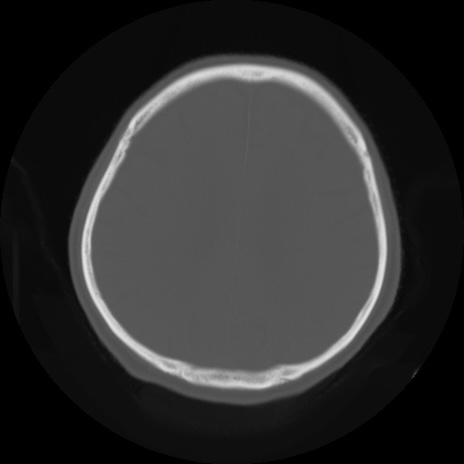

【頭部】症例5 CT(横断像)

【症例】80歳代 男性

【主訴】頭部打撲

【現病歴】外出先で椅子から立ち上がる際に、つまづいて後方へ転倒し受傷。転倒時に意識はあった。

【既往歴】高血圧、不整脈、アルツハイマー病

【身体所見】BP 217/71、HR 96、JCS1-1、 難聴あり、顔色良好、右後頭部に擦過創あり。神経学的異常なし。

症例5の画像所見と診断は?